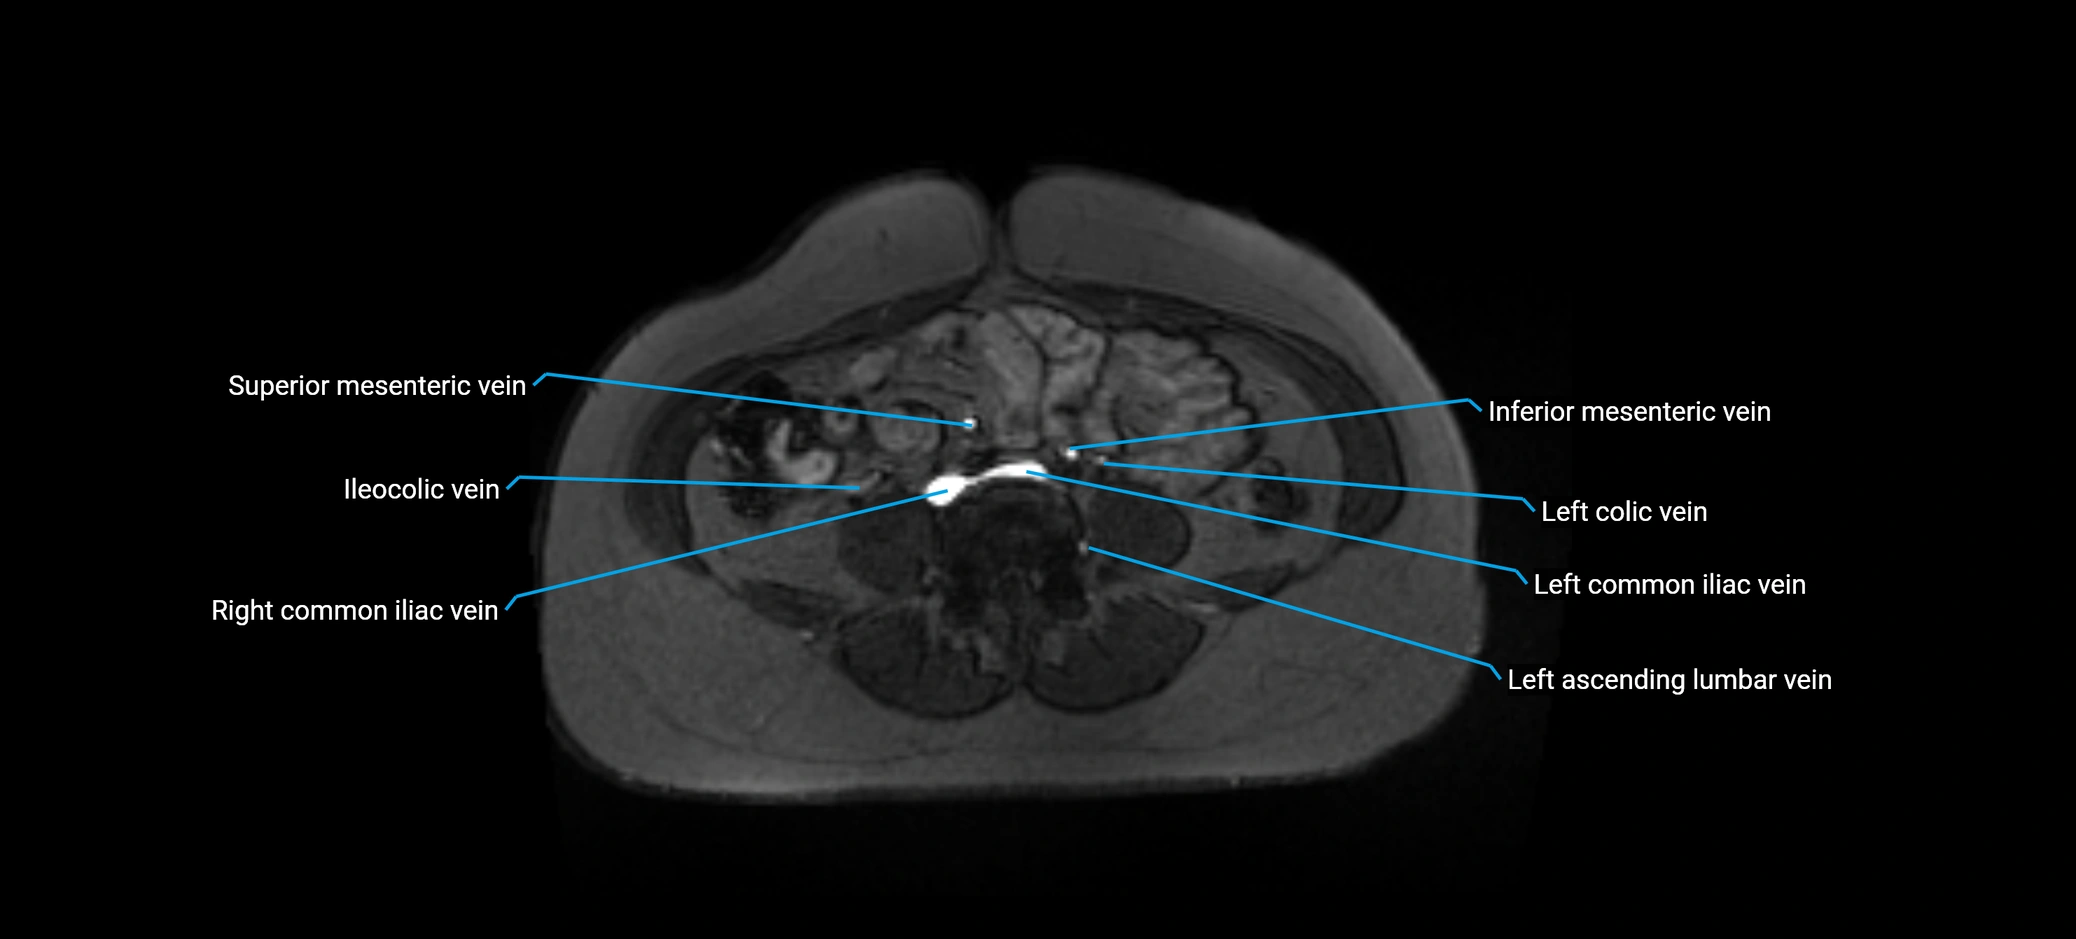

MRI image

image